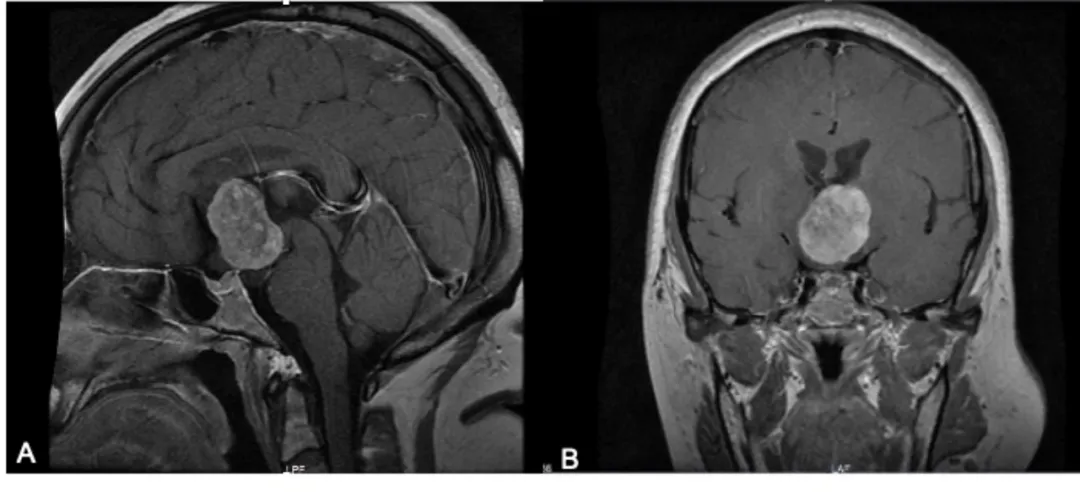

诊断方法主要包括磁共振成像(MRI)和活检术是确诊的主要依据,MR显示通常位于前三脑室内边界清楚的卵圆形或分叶状的肿块。T1与脑实质等强度,增强后明显均匀强化。受压相邻中枢神经结构(包括视神经束、基底节和内囊)可出现血管源性水肿,增强后明显强化,瘤周“八字水肿征”。

头颅MRI增强扫描示鞍上占位,边界较清。T1WI呈等低信号,T2WI呈不均匀等高信号,增强后病灶呈不均匀强化,邻近侧脑室、三脑室、视神经受压。A示增强矢状位,B示增强冠状位。